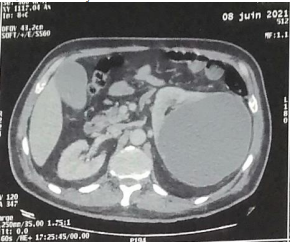

Despite 48 hours of antibiotic treatment, there was no clinical or biological improvement. A contrast-enhanced abdominal and pelvic CT scan (excretory phase) confirmed the findings without providing further diagnostic clarity (Figures 1 and 2)

Figure 1: Coronal section from an abdominal CT scan in the arterial phase showing a 17 cm renal cyst with contrast-enhancing wall and hypodense content.